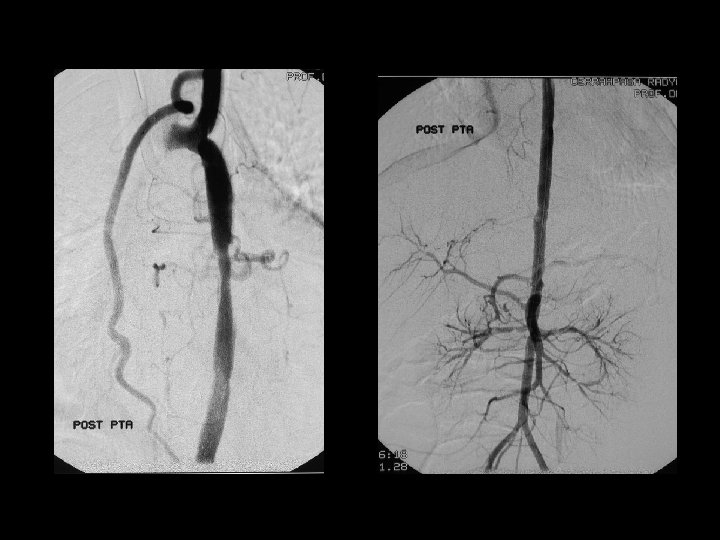

Fibromuskular displazi (FMD) Sağ renal arter stenozu; PTA